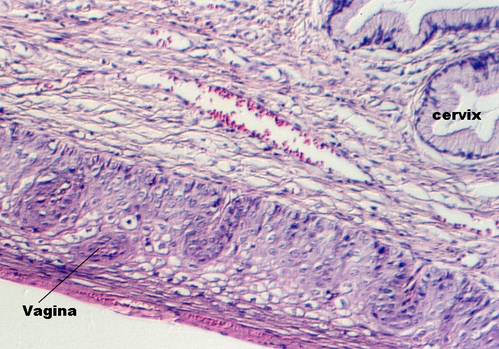

Moving toward the vagina, one can see the abrupt transition between the cervical glands and the stratified squamous epithelium of the vagina. The region showing the vaginal and cervical areas juxtaposed is seen in the following photo.

A low magnification view of the vagina is shown in this photograph. The epithelium is stratified squamous. Underneath the epithelium is a lamina propria. Note that there is no muscularis mucosa. You will use this feature to distinguish the vagina from the esophagus. Another difference is the fact that the vagina has some tight junctions which, along with a lipid secretory material, make the epithelium a permeability barrier.